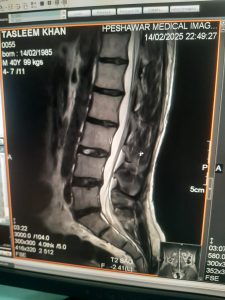

Successful Installation and Commissioning of Hitachi Echelon 1.5T MRI at Peshawar Medical Imaging (PMI)

This milestone marks our ongoing commitment to delivering reliable and high-performance MRI solutions throughout Pakistan. Congratulations to our dedicated engineering team for their excellence and professionalism. We are proud to contribute to advancing diagnostic imaging capabilities in the region.